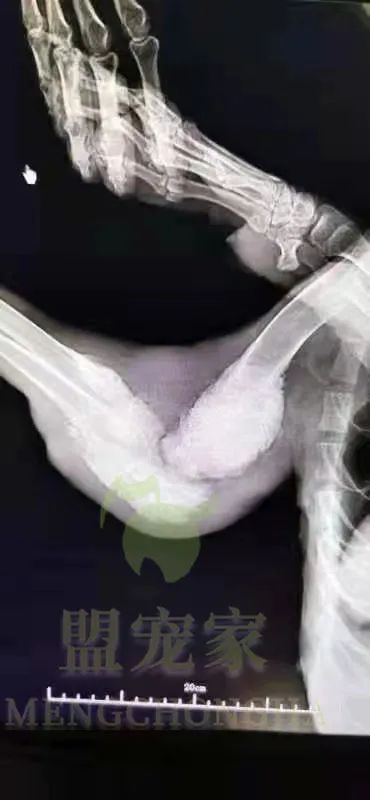

△x光诊断结果

原来,我不仅换上了骨癌, 而且还是恶性的, 必须马上手术和化疗,而且治愈的几率非常非常小。